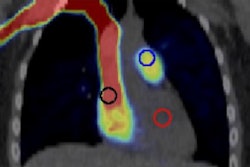

Also, with the dangers of vaping highlighted in news headlines recently, timely research by a team at the University of Pennsylvania points toward a unique inflammatory response due to its use. The findings are based on the first PET imaging study in electronic cigarette users.